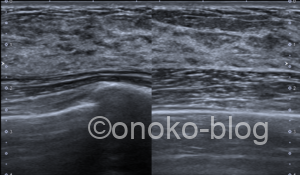

実際のエコー画像です。

※2枚目は乳頭下の画像です

『超音波画像では,皮下脂肪組織が減り,乳腺が厚みを増し,その内部の低エコー(豹紋パターン)がはっきりしてくる』

『クーパー靭帯を押し広げるようにして乳腺が増生している様子が観察される』

正常乳腺と比べてみると、

内部の低エコー像が明瞭ですね。

押し広げられたクーパー靭帯は今回確認できなかったのが残念です。